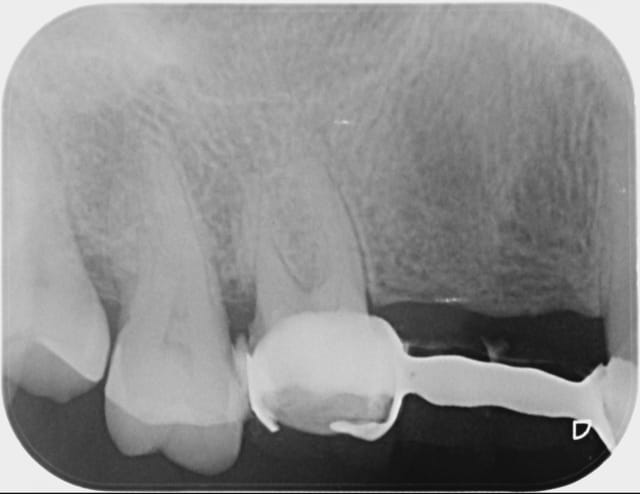

je vois cette patient de 62 ans pour la premiére fois en novembre 2010, elle me demande une rehabilitation des secteurs édentés, sont absentes 14, 15, 47,et 36 toutes les autres dents sont ultra saines, pas de tartre, un excellent controle de plaque, seul "hic" la patient à une valvulopathie qui la classe dans les patients à risque A...

Puis le temps passe, elle reviens en urgence la semaine derniére pour une pulpite et saignement des gencicves,

et là je découvre ça...(cf radio) fait au bled il y a un mois, pour une fortune là bas en depis de tout ce qu'on s'est acharné à lui expliquer. dommage.

Sinon, j'en ai déjà démonté des merdes comme celle-là, te fais pas trop de souci, un coup de fraise dans la couronne et tu es déjà dans la dentine... enfin dans l'émail vu l'épaisseur de la "préparation".

Le seul défaut, c'est que la merde qui sert de chape (sous l'espèce de résine dégueulasse qui sert de céramique, et qui est probablement responsable de l'état de la gencive) colorie les dents en noir façon dent enduite de pétrole.